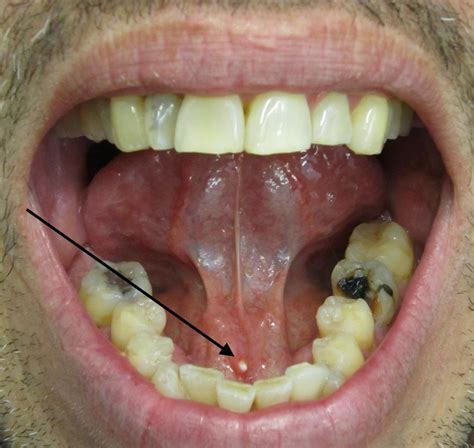

Your body has three main pairs of salivary glands: the parotid (near the cheeks), the submandibular (under the jaw), and the sublingual (under the tongue). Saliva is essential for digestion, keeping your mouth moist, and protecting your teeth from decay. A salivary gland stone forms when the chemicals in your saliva—such as calcium phosphate and calcium carbonate—crystallize and clump together. These hard, pebble-like stones can range in size from tiny specks to large, obstructive masses that significantly impede saliva production.

Most stones form in the submandibular glands, largely because the saliva produced there is thicker and the duct pathways are longer and more convoluted, making them more prone to blockages.

• Visible swelling under the tongue or near the jawline.